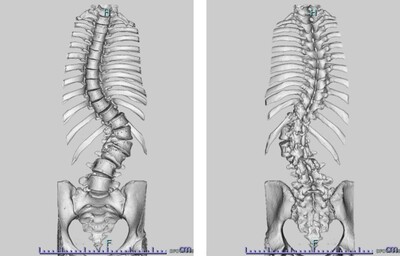

思春期特発性側弯症の全脊椎レントゲンで背骨が大きくSの字に曲がっています。最も曲がっている箇所は80°で、高度側弯に分類されます。後方からの脊柱側弯矯正術で真っ直ぐになっています。

また、側弯の患者さんは一般的にフラットバックと言って背骨の生理的後弯(背中の丸み)が失われています。この症例も胸椎後弯角は5°で典型的なフラットバックを呈しています(正常は20°~30°程度です)。この影響は頸椎の形態にも影響を及ぼし、この症例も頸椎が既に後弯(正常は前弯)しています。(黄色矢印)

ストレートネックという頸椎の前弯が消失して頸部の愁訴が出現する病態は広く知られていますが、更に変形が進行した頸椎と考えて下さい。

以前はこのフラットバック(生理的胸椎後弯の消失)を治すことは困難でしたが、当院では手術方法の様々な工夫により生理的胸椎後弯の復元を行っております。この症例は術後に胸椎後弯角が26°と改善しており、生理的な胸椎後弯が形成されています。さらに頸椎後弯にも良い影響を及ぼし、術後は頸椎前弯化が得られつつあるのが分かります。(黄色矢印)

他、側弯変形は必ず大なり小なりの回旋変形を伴います。脊柱の回旋変形は胸郭(肋骨)の回旋につながり、これにより側弯の患者さんは背中の片方が出っ張っています(多くは右)。リブハンプと言いますが、脊柱変形矯正によりこの回旋変形も改善します。この症例も術前に肋骨がかなり隆起していますが、術後にこの隆起がかなり減じているのが分かります。(赤矢印)